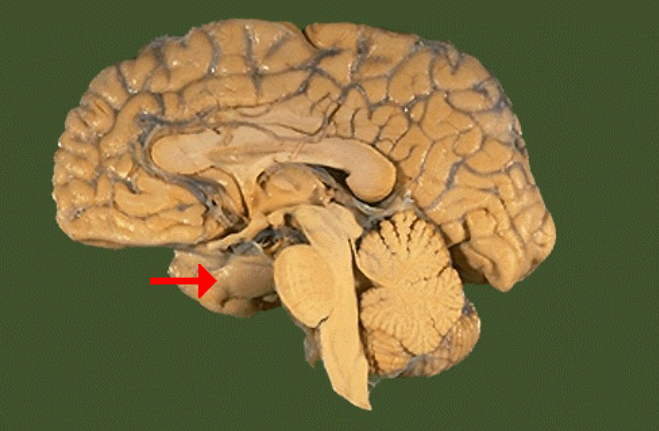

Label this brain part

Mammillary body

Name this brain structure

Temporal lobe

Label this brain structure

Amygdala